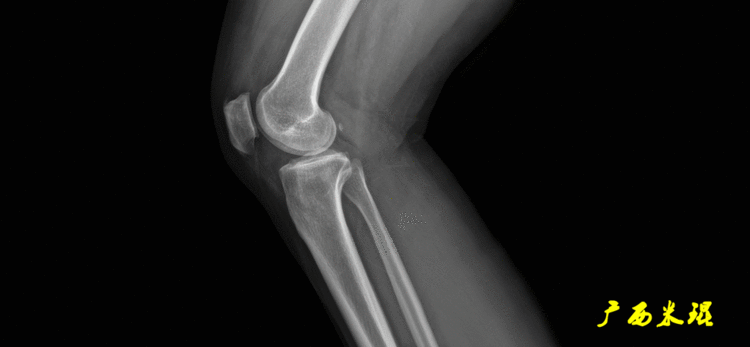

站立侧位(矢状面)股骨头中心与踝关节中心的连线也通过膝关节中心,这也是下肢的机械轴线,这也是下肢力线。

矢状面的下肢力线常常被医生忽视,其实它的改变也是膝关节疼痛的常见原因。

侧位为沿胫骨平台软骨下骨平面的直线,通常与胫骨干有10°±2°的后倾。

胫骨近端后倾角(PPTA):胫骨平台关节面有平均10°的后倾,其中内侧后倾约12°,外侧后倾约7°。矢状面上胫骨平台的切线与胫骨解剖轴形成的夹角叫胫骨近端后倾角,正常为80°±3°。

胫骨远端前倾角(ADTA):矢状面上胫骨远端的关节切线与胫骨解剖轴形成的夹角叫胫骨远端前倾角,正常为80°±2°。